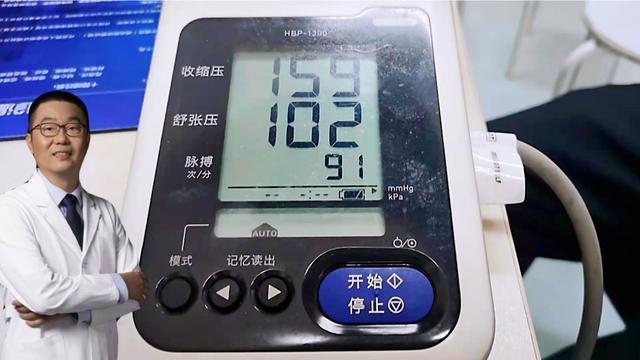

2) L'hypertension artérielle, qui modifie le débit et la fluctuation du flux sanguin, a également tendance à provoquer la formation de caillots sanguins ;

Outre certaines mauvaises habitudes de vie qui peuvent facilement conduire à un infarctus cérébral, l'ignorance et le manque d'attention à la prévention des maladies constituent également un facteur clé. Pour certaines maladies de base qui peuvent facilement provoquer un infarctus cérébral, il est nécessaire d'intervenir raisonnablement le plus tôt possible, par exemple en contrôlant la tension artérielle et la glycémie, en prévenant les infections, etc.

Tout d'abord, nous devons comprendre les facteurs de risque de l'AVC. Il existe de nombreux facteurs de risque d'AVC, notamment l'âge avancé, la race et les antécédents familiaux d'AVC, qui sont des facteurs de risque incontrôlables, tandis que l'hypertension artérielle, les maladies cardiaques, le diabète sucré, l'hyperlipidémie, l'obésité, le tabagisme et les antécédents d'AVC ou d'accident ischémique transitoire sont des facteurs de risque contrôlables.

Bien que la vie économique dans les zones rurales se soit considérablement améliorée ces dernières années, la plupart des habitants ne sont pas conscients de la nécessité d'effectuer des examens de santé annuels. J'ai vu de nombreux patients des zones rurales, et l'hypertension et le diabète sucré ont été détectés dès leur admission à l'hôpital pour examen, et lorsqu'on leur a demandé leurs antécédents médicaux, les patients et les membres de leur famille n'étaient pas au courant, affirmant que les patients étaient en bonne santé auparavant. L'hypertension et le diabète sucré sont des facteurs de risque très courants d'accident vasculaire cérébral. Ils induisent et accélèrent l'athérosclérose cérébrale et peuvent également augmenter le risque de thrombose et d'embolie cérébrale par de multiples voies.

2. Pression artérielle élevée

La Chine compte 2 à 4,5 milliards de patients hypertendus, dont une grande partie vit dans les zones rurales. Il convient de noter que de nombreux patients atteints d'infarctus cérébral dans la Chine rurale présentent en fait une hypertension artérielle non contrôlée à long terme avant la survenue de l'infarctus cérébral. L'infarctus cérébral est l'organe le plus susceptible d'être endommagé par une hypertension artérielle non contrôlée à long terme. C'est pourquoi le Dr Zhang s'est donné beaucoup de mal pour nous donner toutes ces informations, afin que nous soyons attentifs à la gestion de notre propre tension artérielle, et ce n'est que lorsque la tension artérielle sera conforme aux normes que nous pourrons réduire davantage l'incidence de l'infarctus cérébral. Ce problème est plus fréquent dans les zones rurales de la Chine, et les habitants des zones rurales devraient progressivement commencer à s'intéresser à l'hypertension en tant que problème de santé majeur.

- La tension artérielle, la glycémie et les lipides sanguins doivent être activement contrôlés en général pour éviter les maladies cardiovasculaires. Il est important de maintenir une tension artérielle stable, car une tension trop élevée ou trop basse peut provoquer un accident vasculaire cérébral.